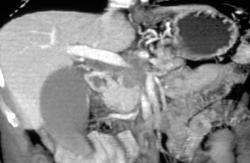

Cystadenoma of the Pancreas